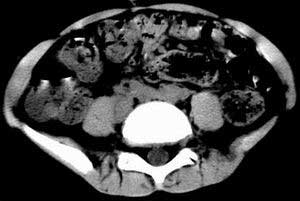

| 患者,男,9岁,因右下腹包块入院,血象不高,不规则发热,常超40度。 平扫: ![]() ![]() ![]() ![]() ![]() ![]() ![]() ![]() ![]() ![]() ![]() ![]() ![]() ![]() ![]() ![]() ![]() ![]() 增强: ![]() ![]() ![]() ![]() ![]() ![]() ![]() ![]() ![]() ![]() ![]() ![]() ![]() ![]() jiajie发言:骶椎右前区不规则软组织肿块,边缘光整,密度均匀,增强后均匀强化,右腹股沟区可见肿大淋巴结,临床有时发热,考虑淋巴瘤,儿童盆腔肿瘤应与神经母细胞瘤和横纹肌肉瘤鉴别。 longzhanghui发言:印象:盆腔右后壁不规则软组织肿块,并向前延伸.似为多个肿块融合,呈中等强化.初步考虑淋巴瘤. 听蝉观竹发言:右侧髂内、外组淋巴结肿大,从其形态和融合的情况看,同意大家意见-----考虑恶性病变,但是9岁男孩还要注意检查睾丸情况,有无隐睾? 常常类似情况是隐睾发生精原细胞瘤淋巴结转移,这个病例也要注意这一点!!! 广东凌发言:大家好,在这里我想说一下个人观点,我建议上传图片的同志能否辛苦一点就是把病史和图片都上传完整一点,比如这个病人的腹膜窗,并且这个病人的肠道的准备也是不怎么好,就从现有的质料看:病灶属于淋巴结肿大当无大的争议,有融合趋势,其内无坏死,边缘强化为主,故考虑:淋巴瘤!建议用腹膜窗看一下和肠道的关系! 阿圣发言:病灶属于淋巴结肿大当无大的争议,有融合趋势,其内无坏死,边缘强化为主,故考虑:淋巴瘤 结果是:淋巴瘤 病例来源:ct762。由宁静致远发布: http://www.radinet.com.cn/forum_view.asp?forum_id=4&view_id=2182 |